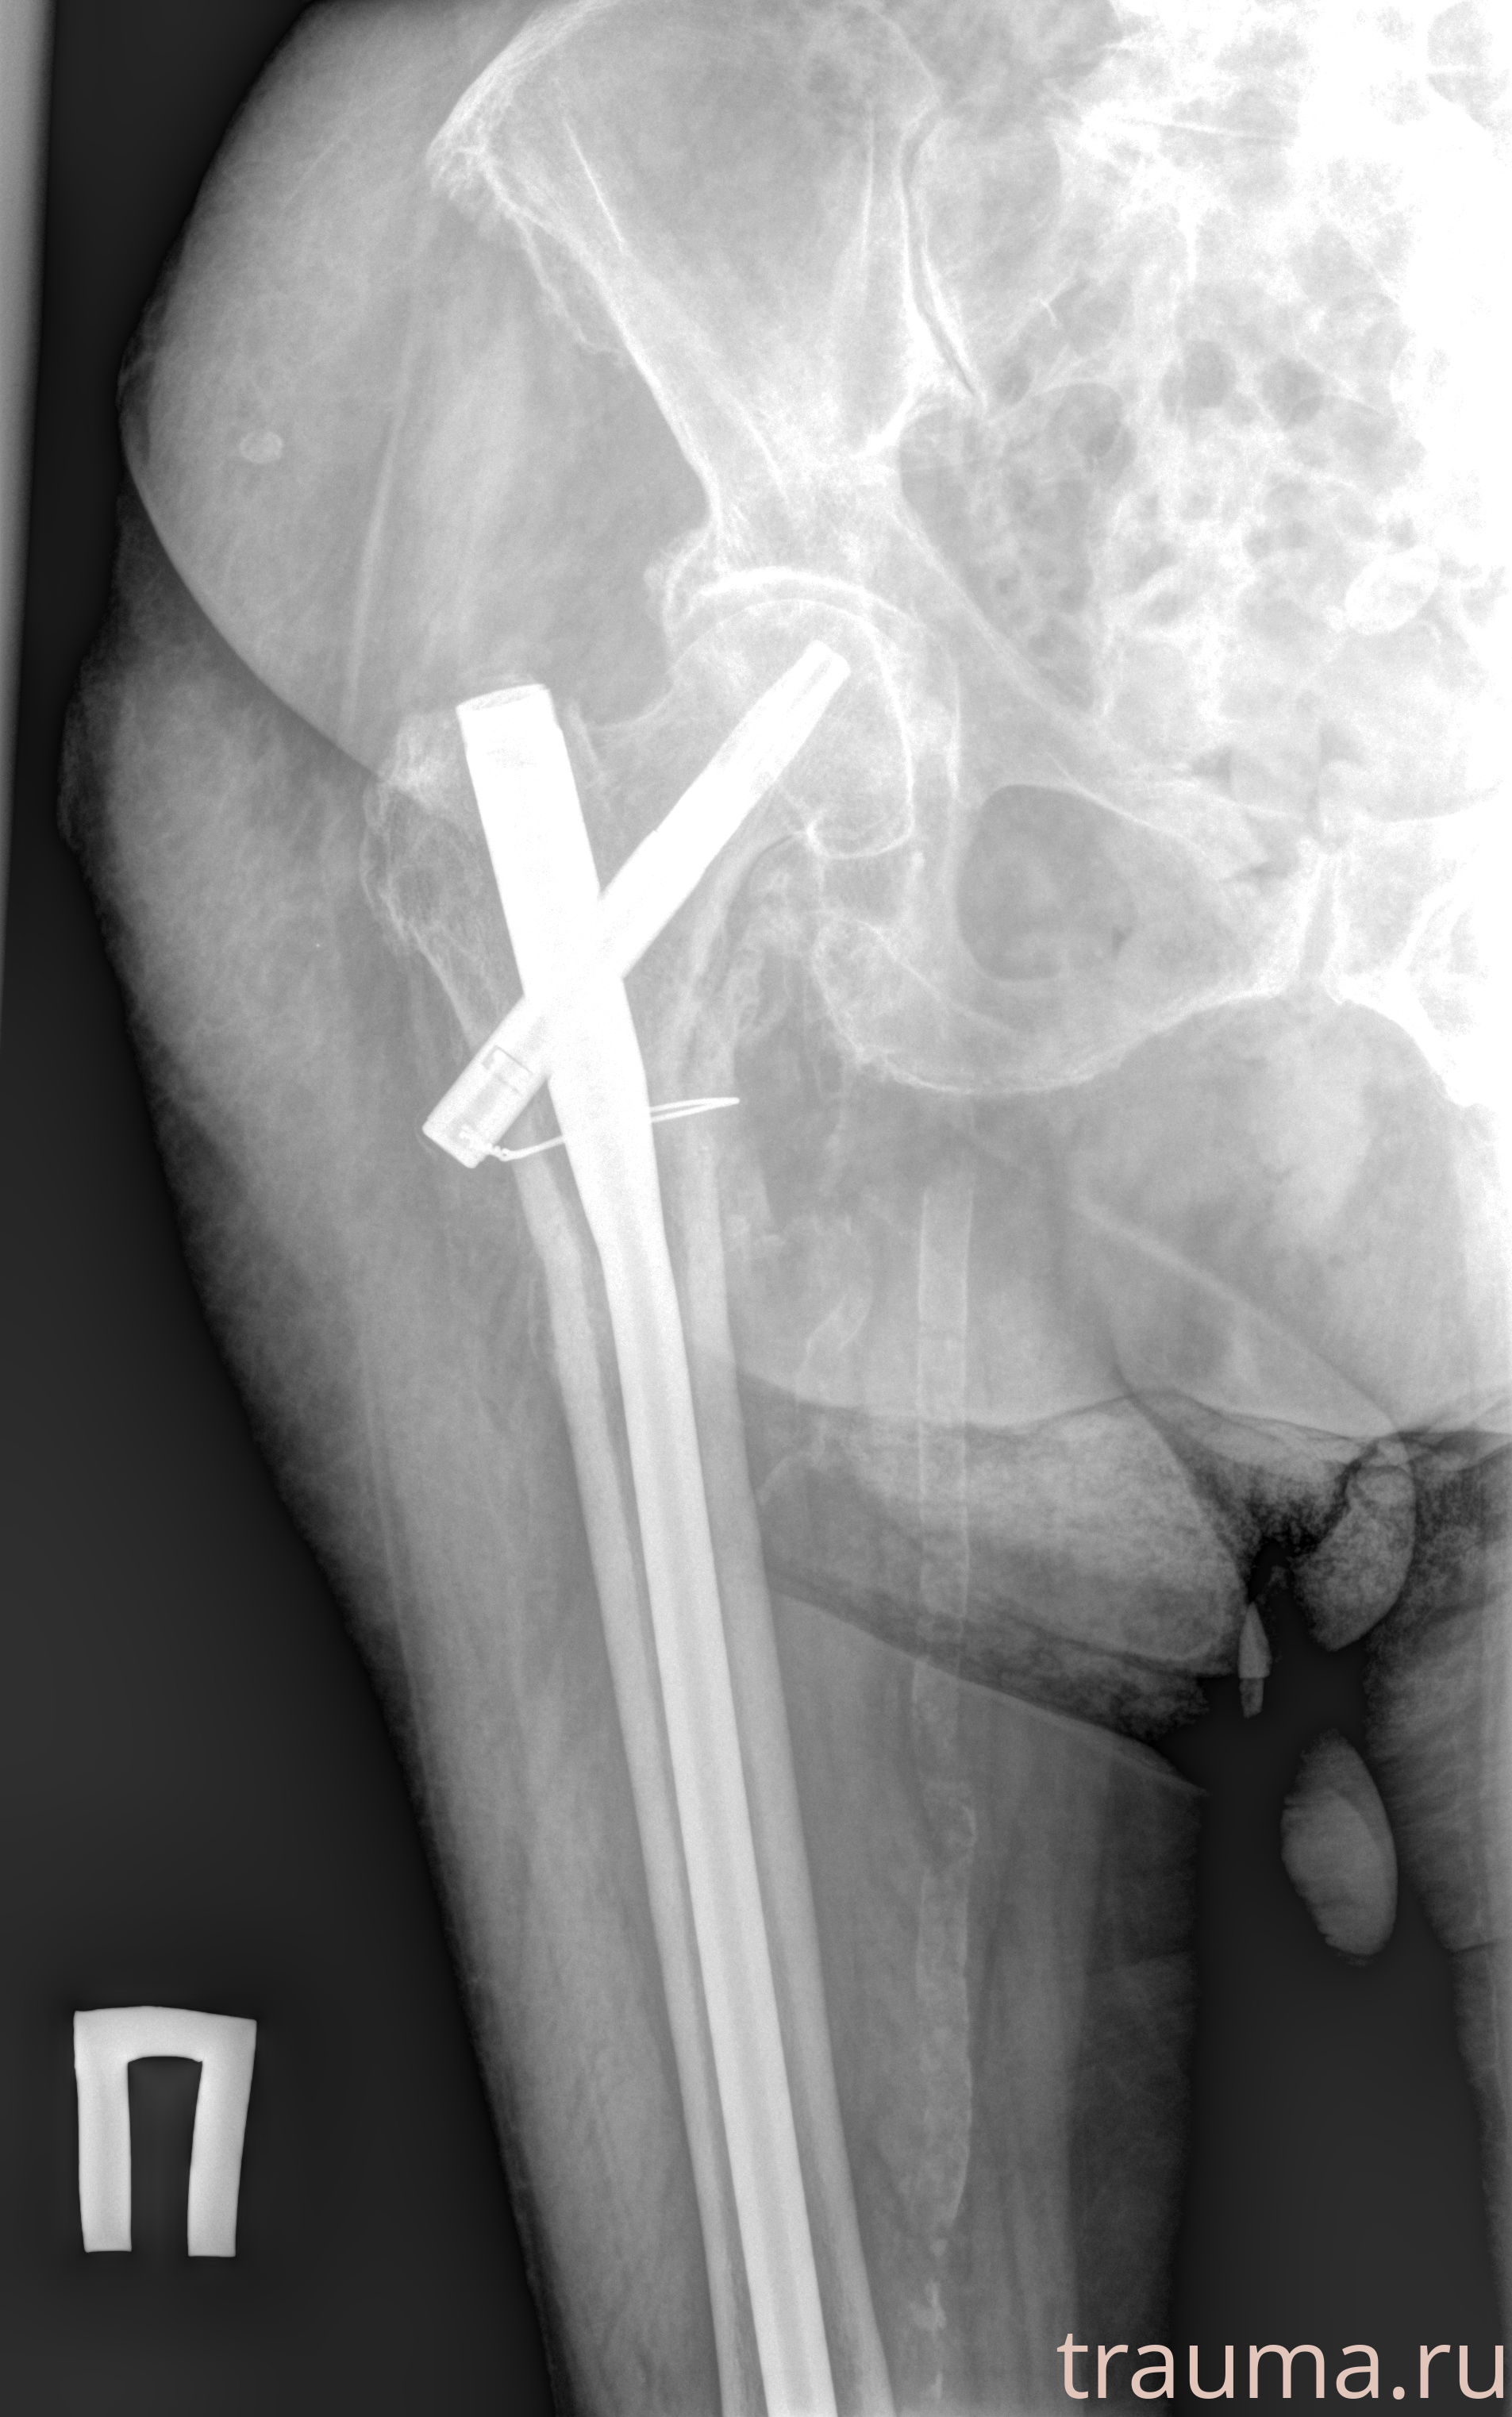

Рентгенограммы

Рентген на дому: по вашему адресу приезжает врач-рентгенолог, травматолог-ортопед с мобильным рентгеновским аппаратом, проводит диагностику травмы или заболевания, делает необходимые рентгенограммы, дает рекомендации по дальнейшему лечению. Получить качественные снимки в домашних условиях возможно благодаря уникальной методике, разработанной МосРентген Центром для института  Склифосовского